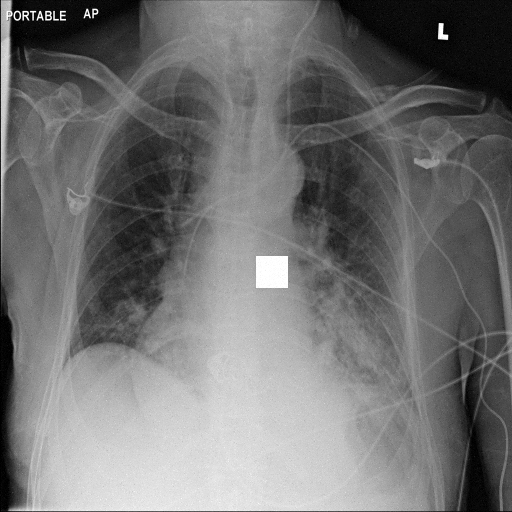

Refer to caption

(a) Original

case 1

(b) ϵ=103HWitalic-ϵsuperscript103𝐻𝑊\epsilon=10^{3}\cdot H\cdot W

(c) ϵ=102HWitalic-ϵsuperscript102𝐻𝑊\epsilon=10^{2}\cdot H\cdot W

(d) ϵ=101HWitalic-ϵsuperscript101𝐻𝑊\epsilon=10^{1}\cdot H\cdot W

(e) Original

case 2

(f) ϵ=103HWitalic-ϵsuperscript103𝐻𝑊\epsilon=10^{3}\cdot H\cdot W

(g) ϵ=102HWitalic-ϵsuperscript102𝐻𝑊\epsilon=10^{2}\cdot H\cdot W

(h) ϵ=101HWitalic-ϵsuperscript101𝐻𝑊\epsilon=10^{1}\cdot H\cdot W

(i) Original

case 3

(j) ϵ=103HWitalic-ϵsuperscript103𝐻𝑊\epsilon=10^{3}\cdot H\cdot W

(k) ϵ=102HWitalic-ϵsuperscript102𝐻𝑊\epsilon=10^{2}\cdot H\cdot W

(l) ϵ=101HWitalic-ϵsuperscript101𝐻𝑊\epsilon=10^{1}\cdot H\cdot W

(m) Original

case 4

(n) ϵ=103HWitalic-ϵsuperscript103𝐻𝑊\epsilon=10^{3}\cdot H\cdot W

(o) ϵ=102HWitalic-ϵsuperscript102𝐻𝑊\epsilon=10^{2}\cdot H\cdot W

(p) ϵ=101HWitalic-ϵsuperscript101𝐻𝑊\epsilon=10^{1}\cdot H\cdot W

Figure 2: ϵitalic-ϵ\epsilon-LDP-processed CXR images obtained with DP-GLOW.

In Fig. 1, we show four ϵitalic-ϵ\epsilon-LDP-processed CXR images of clinical cases obtained with the image domain LDP, which directly imposes the Laplace mechanism on the input image, with different privacy budgets together with the original images. Fig. 2 shows four ϵitalic-ϵ\epsilon-LDP-processed CXR images of clinical cases obtained with DP-GLOW and different privacy budgets together with the original images. In case 1 for DP-GLOW, there is decreased permeability in the bilateral hilar regions. Although this hilar opacity tends to be preserved with a larger privacy budget, the entire image is degraded when the privacy budget becomes 101HWsuperscript101𝐻𝑊10^{1}\cdot H\cdot W. A similar tendency is observed in the images of all the four cases for DP-GLOW; for example, in case 4 with ϵ=101HWitalic-ϵsuperscript101𝐻𝑊\epsilon=10^{1}\cdot H\cdot W, the lung opacity suggesting pneumonia in the right lower lung field is well preserved, while the entire image is degraded.